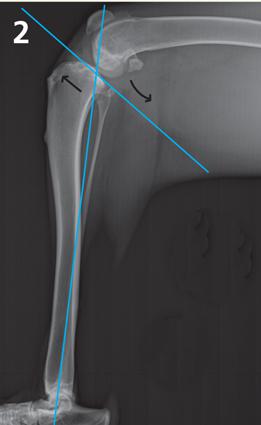

The bone just below the knee or stifle joint is the tibia and the bone above is the femur. The top of the tibia is the tibial plateau. All dogs have a sloping tibial plateau.